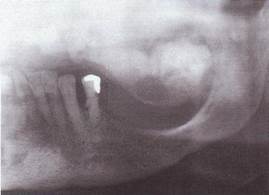

R- картина. В трубчатых кос­тях отмечается разволокнение кортикальных пластинок, склероз губчатого вещества, образуя пятнисто-очаговый "ватный" рисунок. В черепных костях швы почти не определяются. В челюстных костях, кроме типичного "ватного" рисунка определяется преобладание явлений гиперплазии костной ткани, определяется прерывание нижнечелюстного канала в начальном отделе. Отмечается множественная ретенция зубов, сужение периодонтальной щели прорезавшихся зубов.